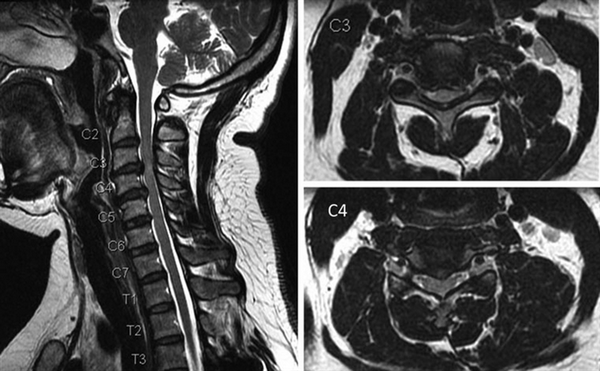

На сериях МРТ, выполненных в аксиальной, корональной и сагиттальной плоскостях, взвешенных по Т2-ВИ, Т1-ВИ и STIR-ИП, получены изображения шейного отдела позвоночника.

Определяется патологический кифоз с вершиной на уровне тел позвонков С5-С6.

Выявляются дегенеративно-дистрофические изменения в виде умеренно выраженного понижения интенсивности сигнала от межпозвонковых дисков в сегментах С2-Th1, со снижением высоты в сегментах С5-С7, а также формирования передних и заднебоковых краевых костных разрастаний. Унковертебральный артроз на уровне сегментов С5-С7.

В смежных отделах позвонков С6-С7 определяются зоны гиперинтенсивного МР-сигнала на Т2-ВИ, STIR-ИП и гипоинтенсивного в Т1-ВИ (вероятно, обусловленные отёком вещества костного мозга).

Определяются неровности смежных замыкательных пластин тел позвонков С5-С7 за счет хрящевых узлов Шморля.

В сегменте С3-С4 под краевыми остеофитами определяется дорзальная медианная протрузия межпозвонкового диска, размером до 2,5мм. Переднее субарахноидальное пространство деформировано. Межпозвонковые отверстия умеренно сужены, достоверных данных за компрессию корешков нервов не выявлено. Передне-задний размер позвоночного канала до 14мм.

В сегменте С5-С6 под краевыми остеофитами определяется задняя диффузная протрузия межпозвонкового диска, размером до 2,5мм. Переднее субарахноидальное пространство деформировано. Межпозвонковые отверстия умеренно сужены, достоверных данных за компрессию корешков нервов не выявлено. Передне-задний размер позвоночного канала до 13мм.

В сегменте С6-С7 под краевыми остеофитами определяется задняя диффузная протрузия межпозвонкового диска, размером до 2мм. Переднее субарахноидальное пространство деформировано. Межпозвонковые отверстия умеренно сужены, достоверных данных за компрессию корешков нервов не выявлено. Передне-задний размер позвоночного канала до 14мм.

Сигнальные характеристики от шейных позвонков не изменены.

Видимые отделы спинного мозга в размерах не увеличены, имеют четкие контуры и однородную структуру, интенсивность МР сигнала не изменена.

Паравертебральные мягкие ткани не изменены.

МР-признаки дегенеративно-дистрофических изменений шейного отдела позвоночника с нарушением статики. Протрузии дисков на уровне сегментов С3-С4, С5-С6, С6-С7. Унковертебральный артроз. Хрящевые узлы Шморля смежных замыкательных пластин тел позвонков С5-С7.